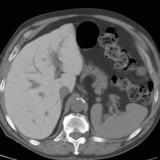

Giant RA CT

Date: 01/07/2012

Views: 2625